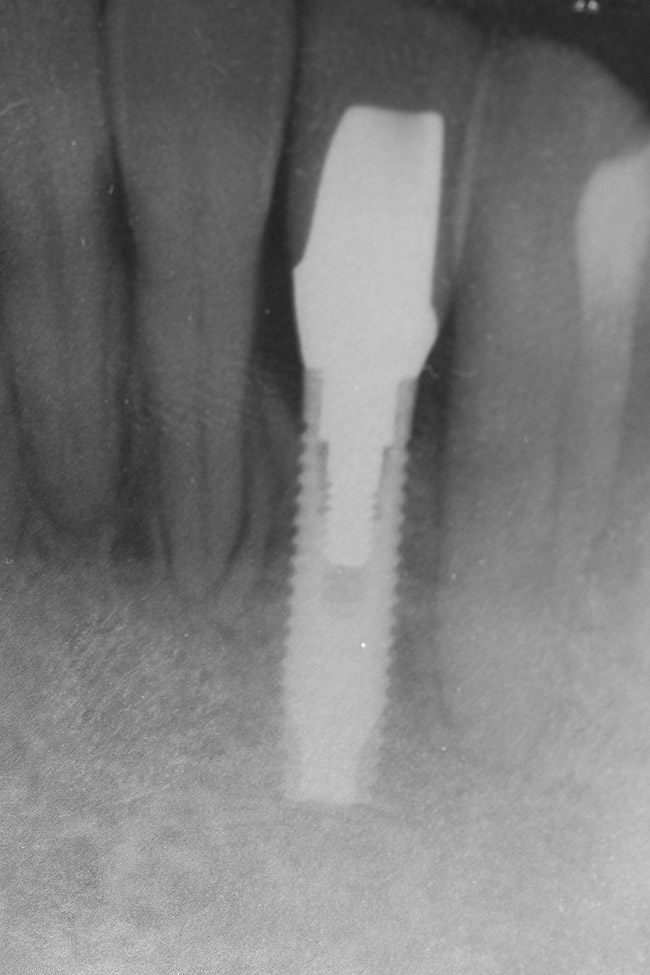

Figure 21  Radiograph of implant in position at the time of surgery of tooth No. 23.

Figure 21

Following the first goal of orthodontia—moving tooth No. 22 to a proper functional and anatomical position—a periodontal reevaluation was performed, demonstrating an improvement in short- and long-term tooth prognosis. At this time, the decision was made to abort continual extrusion of teeth Nos. 21 and 22, although some attachment level discrepancy remained between Nos. 21 and 22 (Figure 14). Implant diagnostics ensued and included mounted study models and a diagnostic wax-up. A scanning appliance was created to demonstrate the desired prosthetic outcome requirements, and the patient was referred for computed tomography (CT) scans. CT scan assessment demonstrated successful orthodontically directed GBR to allow implant placement (Figure 15 through Figure 16). Only minor GBR therapy would be needed and could be accomplished simultaneously with implant installation. Guided implant placement occurred, using an open flap approach (Figure 17). During surgery, root dehiscences were noted on teeth Nos. 21, 22, 24, and 25, as well as the anticipated dehiscence following implant placement at No. 23 (Figure 18). A positioning reference (index) was secured after implant placement to facilitate a provisional prosthesis at stage II surgery. Cortical perforations then were placed adjacent to the implant to encourage angiogenesis (Figure 18), and mineralized freeze-dried bone allograft enhanced with platelet-derived growth factor was placed over the dehiscences for purposes of guided tissue regeneration and GPR (Figure 19). A highly resorbable collagen membrane was placed to stabilize the allograft. The flap was coronally repositioned, and primary-intention wound healing was achieved (Figure 20 and Figure 21). Following 4 months of stage I surgery, implant uncovery and immediate provisionalization was performed in conjunction with connective tissue grafting. Final orthodontic tooth movement then ensued, using the implant as anchorage to optimize end-tooth movements, interroot separation, and the cuspid-protected occlusal scheme. A final impression then was secured, and a zirconia abutment (Figure 22) with an all-ceramic restoration was fabricated for the prosthetic phase completion of No. 23 (Figure 23] through Figure 25).